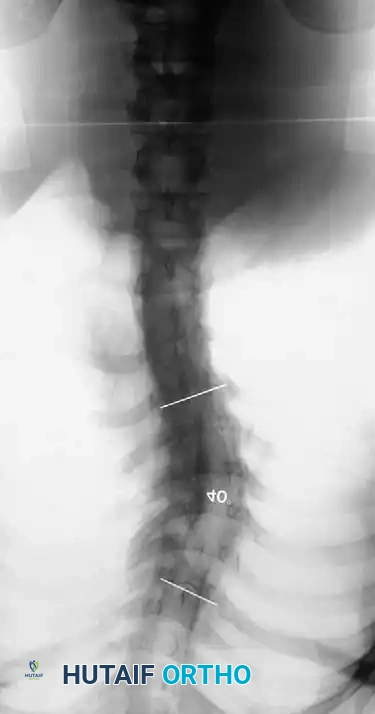

Fig. 38-202: Postoperative radiographs demonstrating anterior fusion with vascularized rib graft and structural strut grafting in a patient with severe dystrophic kyphoscoliosis.

For smaller dystrophic kyphoscoliosis (kyphosis <40 degrees), posterior instrumentation and arthrodesis may be attempted early, but the fusion mass must be explored at 6 to 12 months. If kyphosis exceeds 50 degrees, the combined anterior/posterior approach is non-negotiable. The anterior fusion must extend one or two levels beyond the end vertebrae of the kyphotic segment to prevent junctional failure.